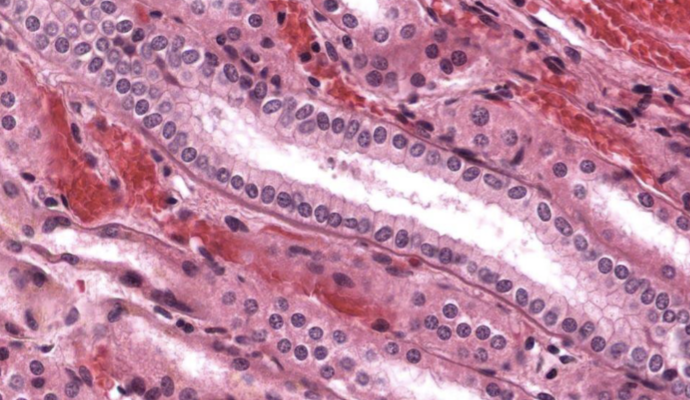

pseudoestratificado